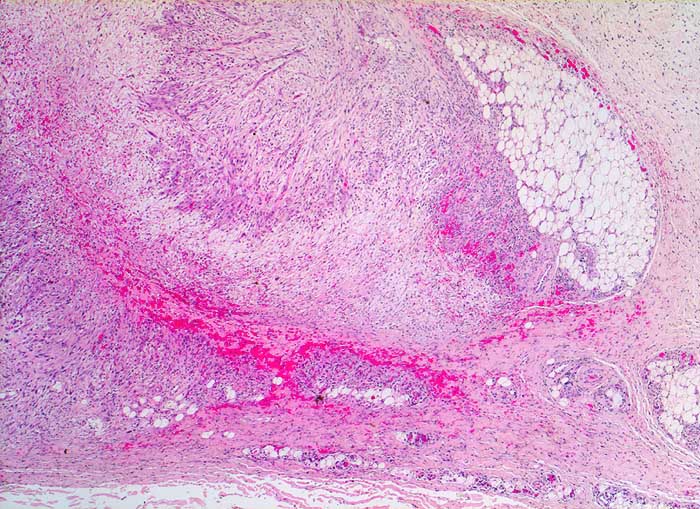

noduläre Fasziitis

Einer Faszie aufsitzende etwas unscharf begrenzte Läsion im Fettgewebe mit alternierend hellen ödematösen Zonen angrenzend an Zonen, die an Granulationsgewebe erinnern.

Rasch gewachsener subkutaner Knoten suprapatellär rechts. Durchmesser 1cm.

Eine der häufigsten Sarkomfehldiagnosen. Im Gegensatz zu den meisten Sarkomen sehr rasches Wachstum, keine wesentlichen Zellatypien, oberflächliche Lage

Histologie

25